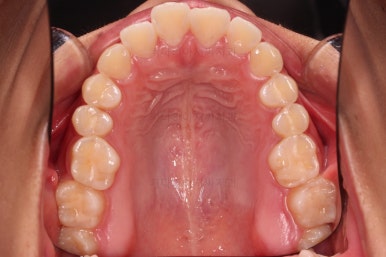

마무리가 잘 되었습니다.

큰 문제는 없었지만, 약간 삐뚤었던 치열이 가지런하게 정렬이 잘 되었고요.

맞물림도 매우 좋고, 뻗친 앞니 각도도 매우 좋아졌습니다.

입 안의 모습만 보면 최상급의 마무리가 되었고요.